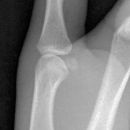

Endgelenksluxation Daumen